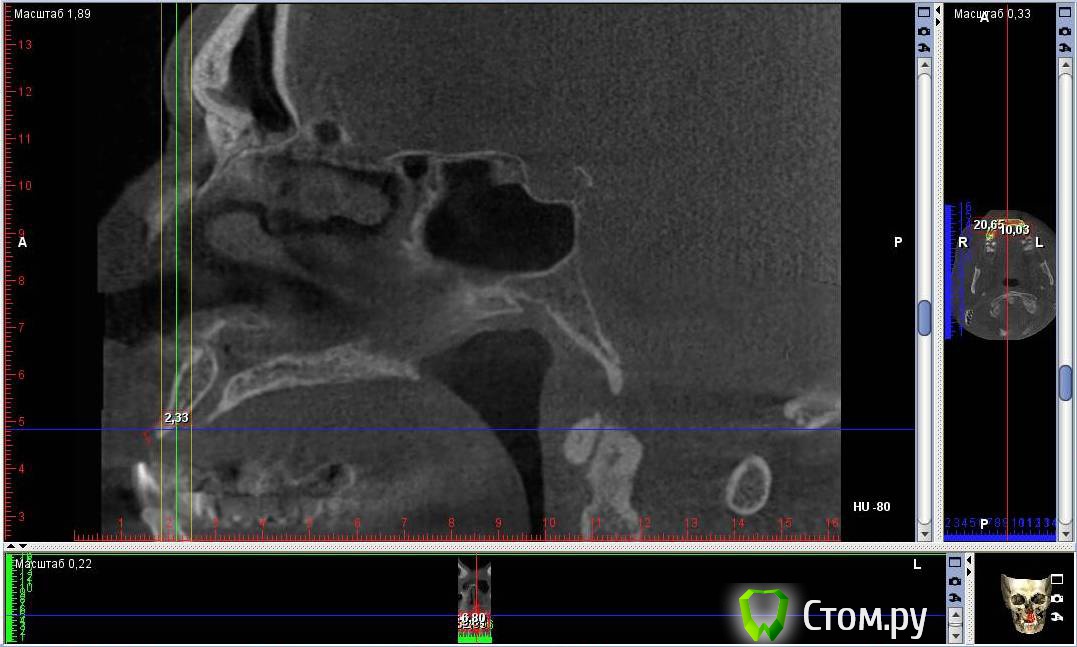

Togha Опубликовано 5 мая, 2014 Поделиться Опубликовано 5 мая, 2014 (изменено) Коллеги, обратился пациент, первый этап работы - устранение адентии между 14 и 23 зубами. По вертикали есть куда разбежаться (до анатомических образований от 17 и более мм), но вот гребень совсем узкий (от 2 до 5 мм), а также широкий резцовый канал (примерно 6.5 мм в диаметре). Между 14 и 23 расстояние 38 мм. Пациент решительно настроен на имплантацию. Хотел бы узнать, какую методику аугментации посоветуете, и как спозиционировать имплантаты? Склонялся к расщеплению гребня, нкр, имплантаты 3.75 мм на 10 мм, сделать мостик предлагает ортопед, на область 13, 11, 21, 22. Но как с расщеплением в зоне резцового канала и куда ставить имплантат 21 (как видно, есть значительное смещение канала от 11 в сторону 21), прямо в канал? Ссылка на DICOM файл http://yadi.sk/d/2vcbkBjaPBRgMСсылка на образ диска с просмотрщиком http://yadi.sk/d/csIsw0mYPBS2x На второй картинке примерно обозначен граница резцового отверстия вертикальными линиями Изменено 5 мая, 2014 пользователем Togha Ссылка на комментарий